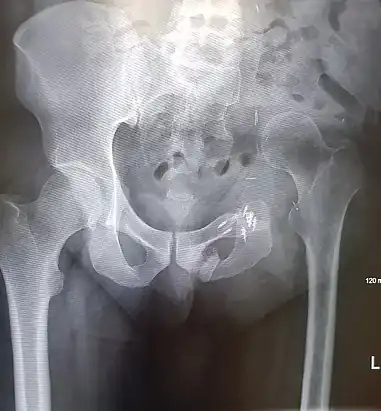

An x-ray of a limb-sparing hemipelvectomy on the left side of a male pelvis taken one month after surgery.